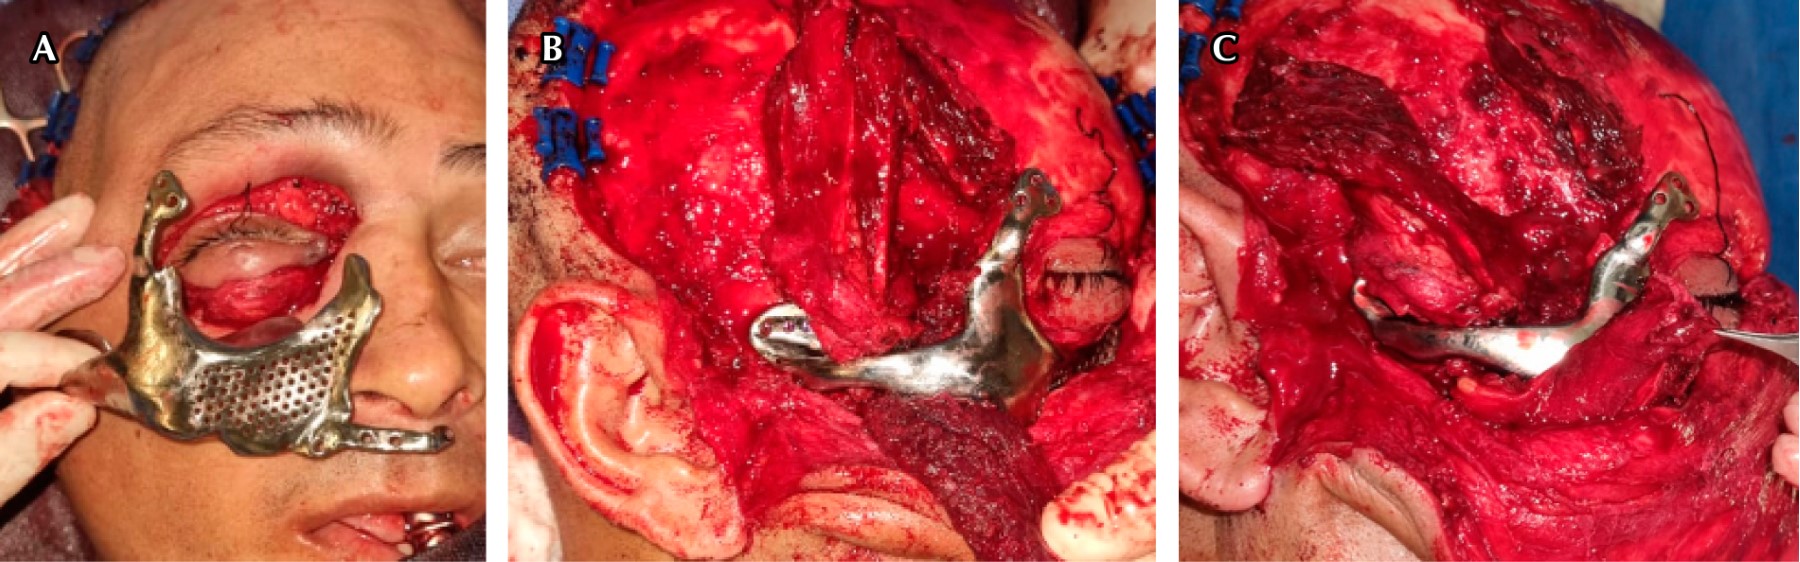

Zygomaticoorbital complex reconstruction with titanium prosthesis: case report

Rodríguez S, Rivas J, Villegas J, García H, Gudiño R, Jaimes J

zygomatic-orbital complex, reconstruction, titanium, temporalis muscle.

Maxillofacial trauma has always been a challenging area for oral and maxillofacial surgeons. Whenever we speak about midface trauma, zygomatic complex is the most common region to treat because of its implications in aesthetic and functional problems that can compromise the nearby eye. In the case of zygomatic complex fractures, most of the time it involves a bone defect in one of its four buttresses, determining the need to reconstruct. Custom made titanium prosthesis offers a lot of advantages in handling and installation, making it easier to adapt in the required region.

Figure 1